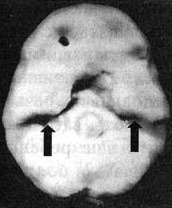

Иллюстрация к книге — Измените свой мозг - изменится и жизнь! [i_070.jpg]

Трехмерное изображение поверхности, вид сбоку.